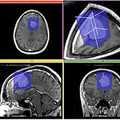

SubvolumeExraction_icon.png(200 × 200 pixels, file size: 73 KB, MIME type: image/png)